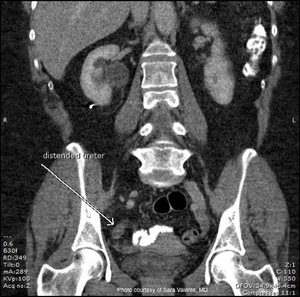

Challenging cases in urology: A case of hydronephrosis, sepsis, and pain

A 61-year-old female complains of acute-onset right-sided flank and abdominal pain. She describes associated nausea, but denied urinary symptoms, hematuria, fever, or chills.